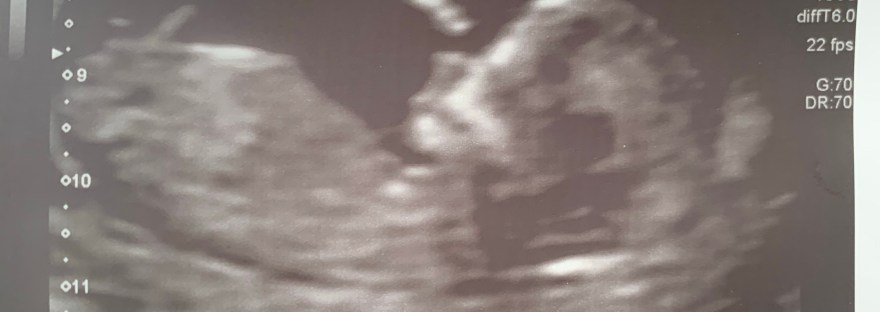

The magical 12 week scan

At last! Getting to know that your little one is doing okay, and being able to tell the world about them